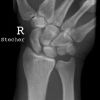

Handgelenk seitlich

Handgelenk, Unterarme, Ellenbogen (gebeugt) liegen mit der Kleinfingerseite streng seitlich auf. Handfläche hat leichte Retroflexion, d.h. der untere Handballen steht leicht vor. Daumen gestreckt über übrige Finger halten. Stellung durch Tasten im Handgelenk überprüfen.

Senkrecht auf Handgelenk- und Filmmitte.

Ulnar und Radius müssen distal übereinander projiziert werden. Os Scaphoideum und Os Lunatum liegen übereinander, ebenso die Mittelhandknochen, bei Verdacht auf Subluxation des Os Lunatums, Zusatzaufnahme in Flextion und Reflextion der Hand notwendig (Stressaufnahme).

Qualitätskriterien

Radius und Ulnar müssen deckungsgleich sein; Mittelhand, Handwurzelknochen und distaler Unterarm sollen abgebildet werden.